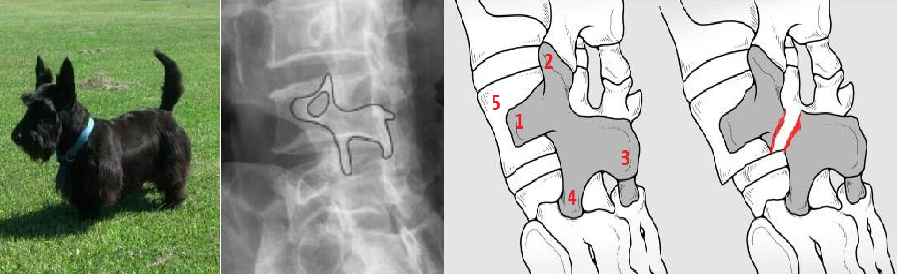

Una interrupción del arco óseo y un deslizamiento del cuerpo vertebral hacia atrás o hacia adelante generalmente se pueden ver en una radiografía (rayos X). Una radiografía oblicua de la columna lumbar es la indicada para identificar la espondilólisis, en este estudio se evidencia el signo radiológico: “perrito escocés- scottie dog sign”.

En medicina se denomina de esta manera porque cada parte del cuerpo del perro representa una porción de la vértebra:

Si en este signo se presenta un collar alrededor del cuello del perro, es indicativo de existe una fractura no desplazada de la parte interarticular (pars interarticularis).